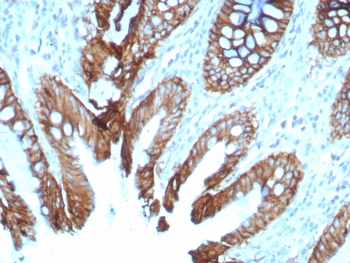

Cadherin 17 Antibody Colon IHC. Immunohistochemistry of Cadherin 17 antibody in human colon tissue. The recombinant mouse mAb clone rCDH17/8512 demonstrates strong membranous HRP-DAB brown staining along the lateral borders of colonic epithelial cells, consistent with Cadherin 17 localization in intestinal epithelium. Staining highlights well-organized glandular crypt structures with preserved epithelial polarity, while surrounding stromal tissue shows minimal background signal. Heat-induced epitope retrieval was performed by boiling tissue sections in pH 9 10mM Tris with 1mM EDTA for 20 minutes followed by cooling prior to incubation.